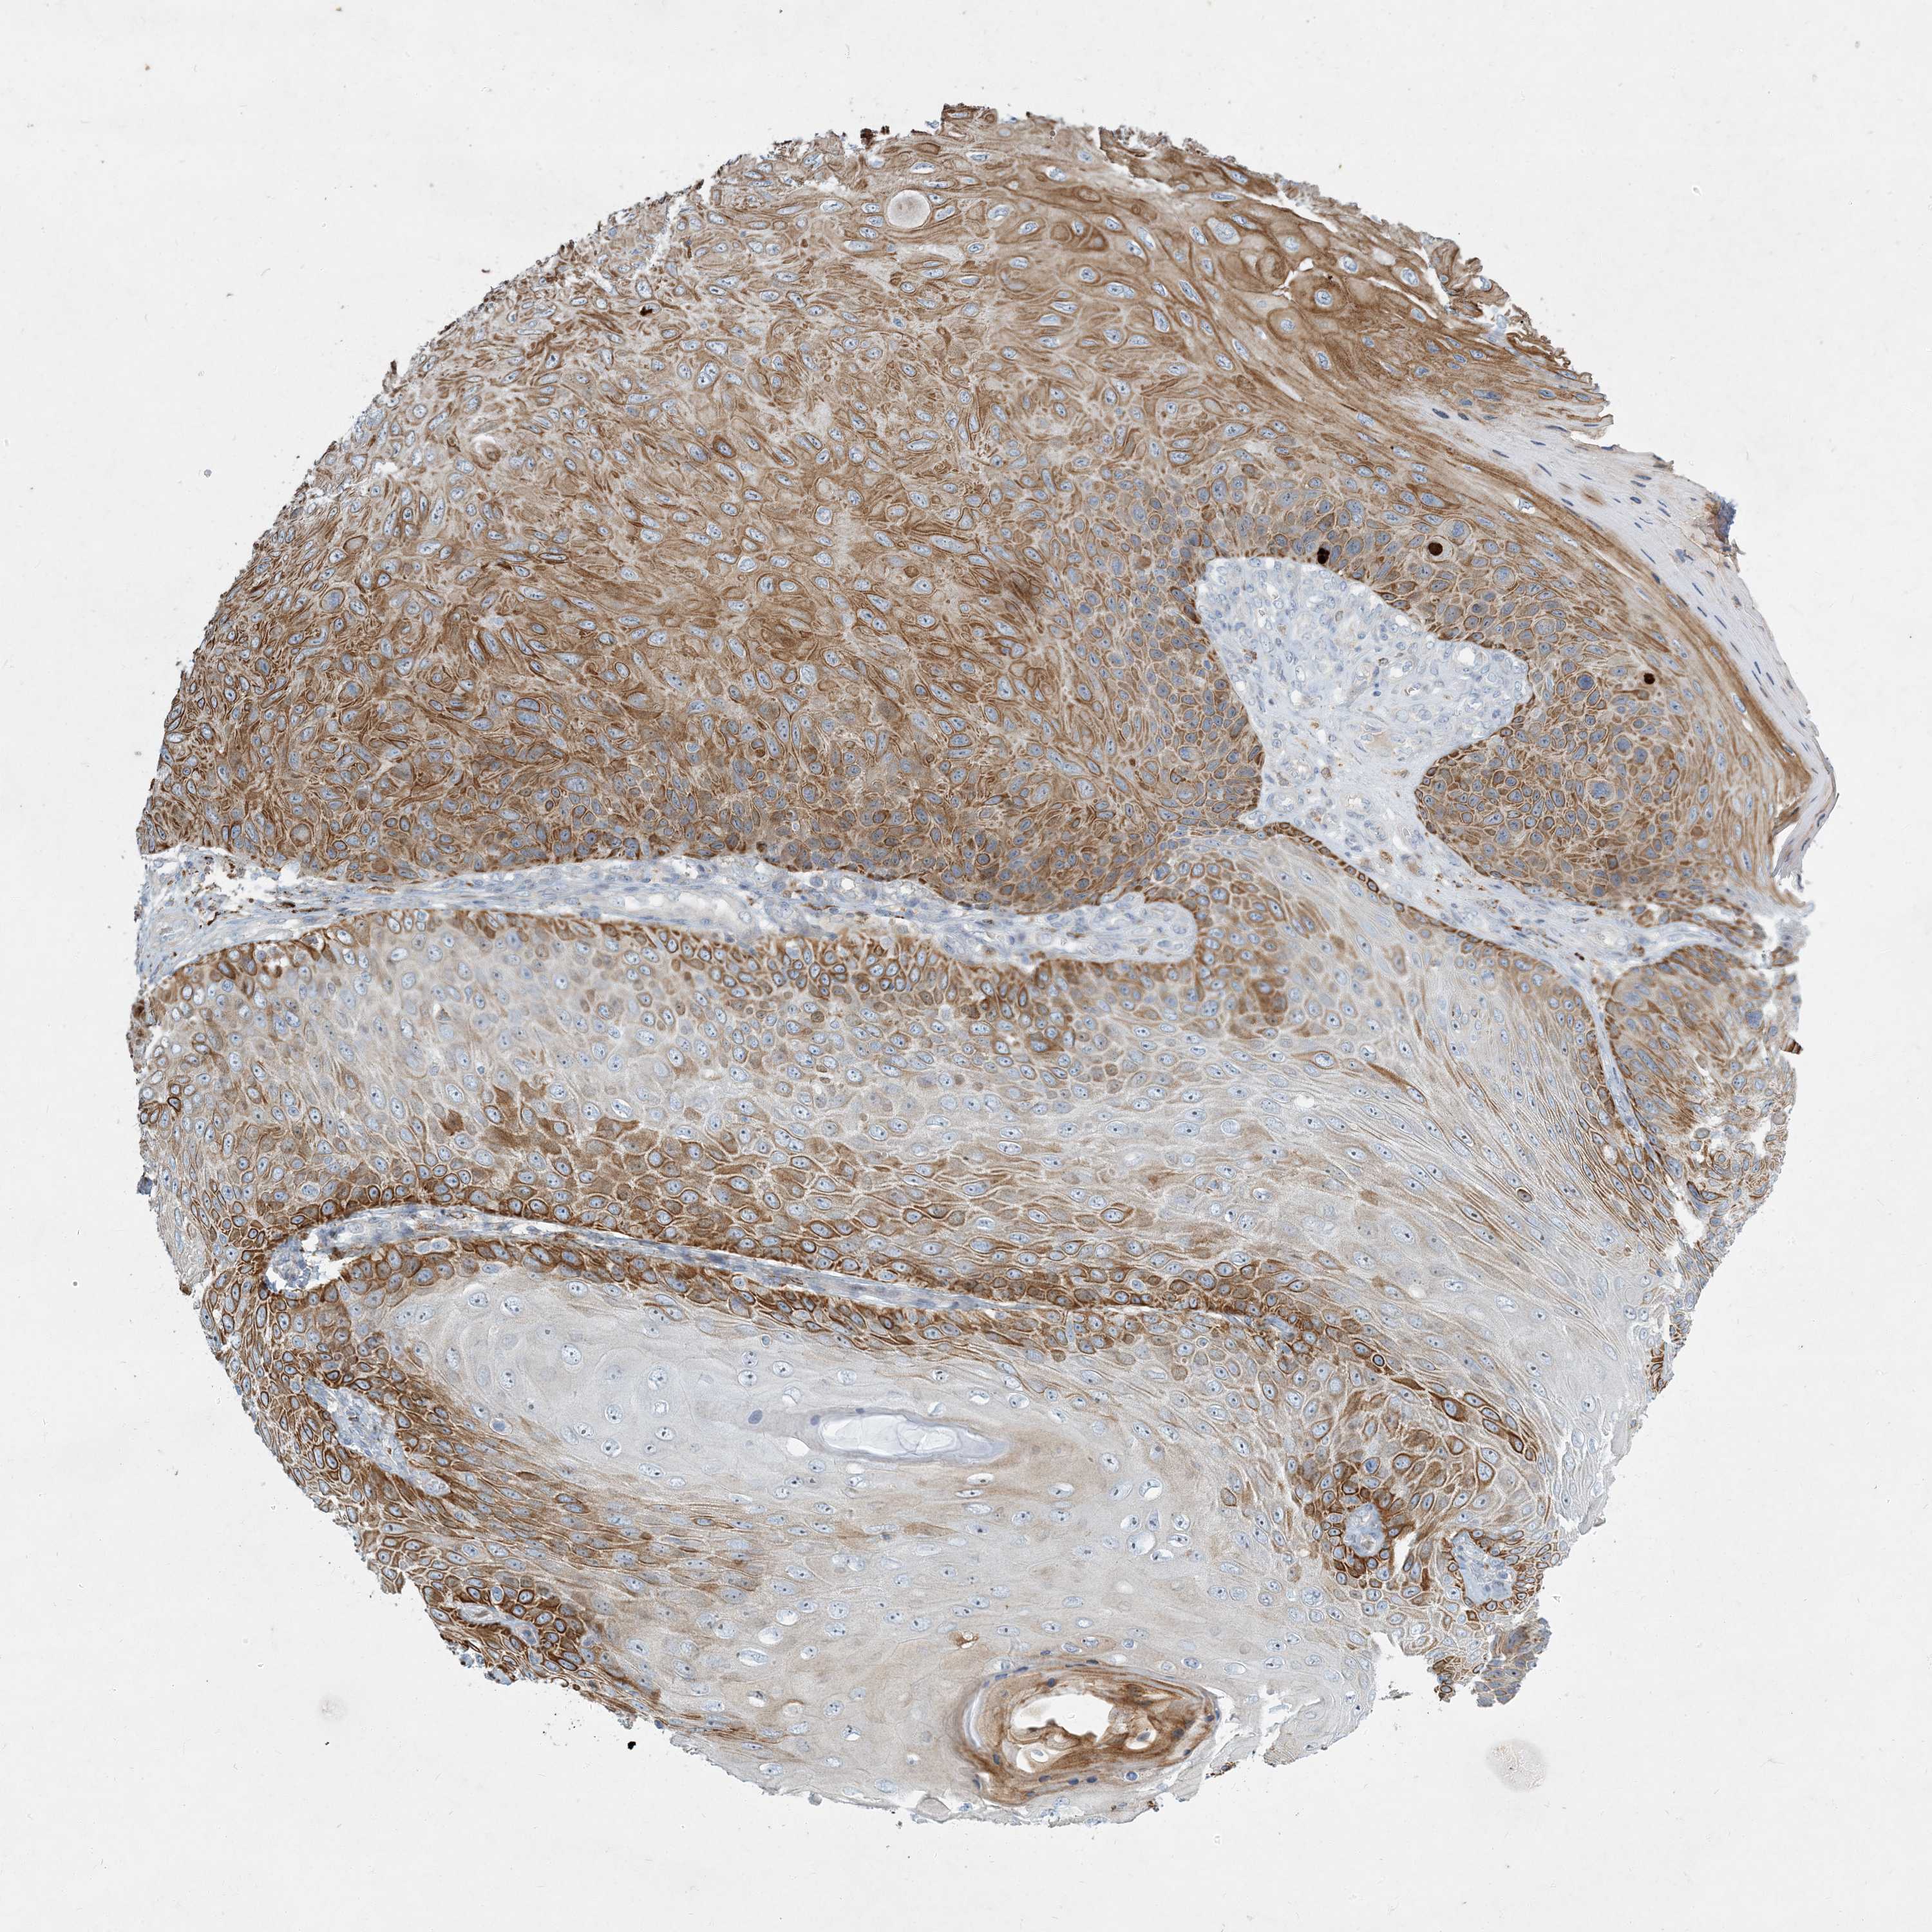

Basal cell and squamous cell cancer

SKIN CANCER - Protein expressioni

A mouse-over function shows sample information and annotation data. Click on an image to view it in a full screen mode. Samples can be filtered based on level of antibody staining by selecting one or several of the following categories: high, medium, low and not detected. The assay and annotation is described here.

Each image is clickable and will lead to virtual microscopy that enables deeper exploration of all samples and also displays staining intensity scores, fraction scores and subcellular localization as well as patient and tissue information for each sample.

Antibody CAB034164

Squamous cell carcinoma, NOS